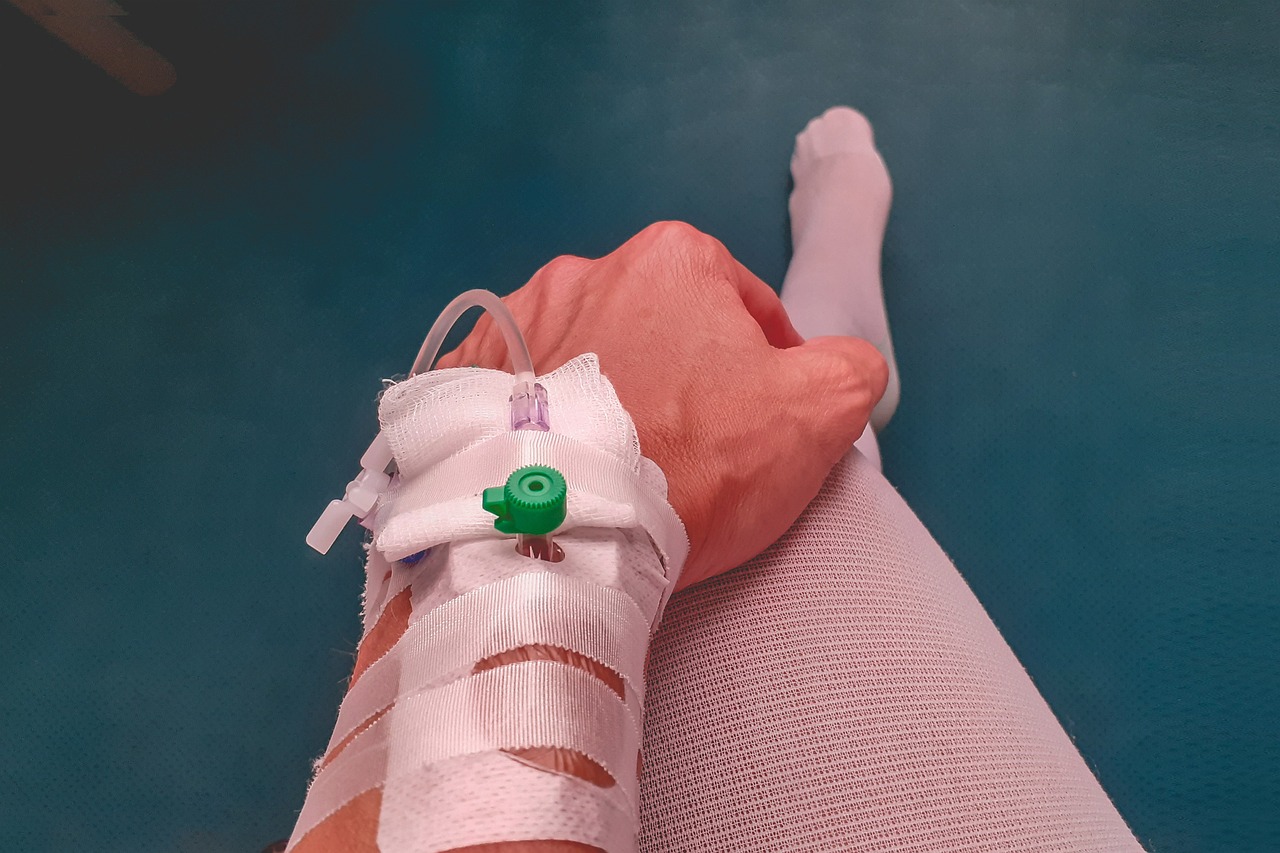

서류에는 반드시 의사 소견서 또는 진단서가 포함되어야 하며, 환자의 일상생활 수행 어려움을 명확히 기재해야 합니다. 방문조사에서도 의료정보가 중요한 참고자료가 되니, 암환자의 경우 전문의의 상세한 진단서가 큰 도움이 됩니다.

장기요양 신청 시 필요 서류

장기요양등급 신청방법을 실제 진행하면서 가장 어려웠던 부분 중 하나가 바로 서류 준비였습니다. 제가 할머니 신청을 도와드렸을 때, 처음부터 모든 서류를 준비해간 덕분에 한 번에 접수할 수 있었는데요. 아래는 공단이 요구하는 기본 서류 목록입니다.

| 진단서 또는 소견서 | 주치의가 작성한 최근 6개월 내 발급 서류 |

저는 미리 병원에 요청해 진단서를 준비했고, 공단 지사에 방문했을 때 직원이 친절하게 서류 점검을 해줘 큰 어려움 없이 진행할 수 있었습니다. 공단 홈페이지 자료실 메뉴에서 서식도 내려받을 수 있으니 사전에 확인해보세요.